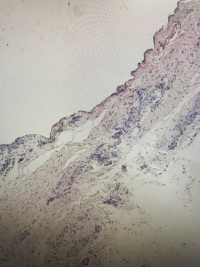

性别年龄40临床诊断

一般病史腹股沟囊性包块,与疝囊壁粘连

标本名称腹股沟包块

大体所见囊实性包块,大小3.8✖️3✖️1.9cm,囊壁厚0.1-02cm

囊性淋巴管瘤?

囊性良性间皮瘤?

有陈旧性出血, 子宫内膜异位也要考虑,问一问病人有没有经期疼痛。

免疫标记对鉴别可能会有所帮助。